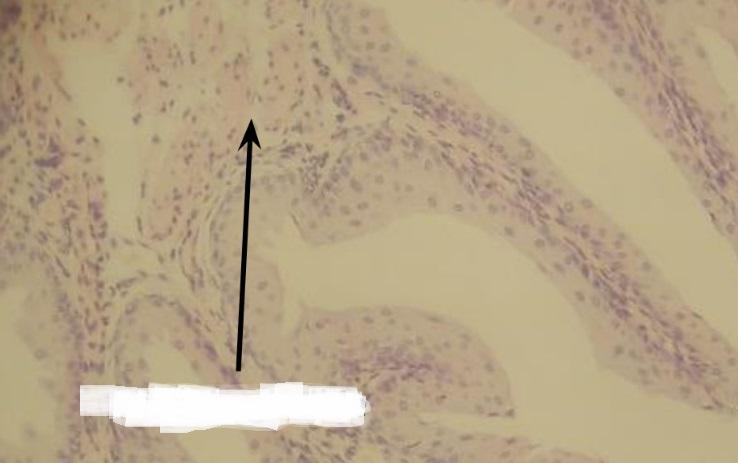

Pytanie 282

przegroda łącznotkankowa (płuco)